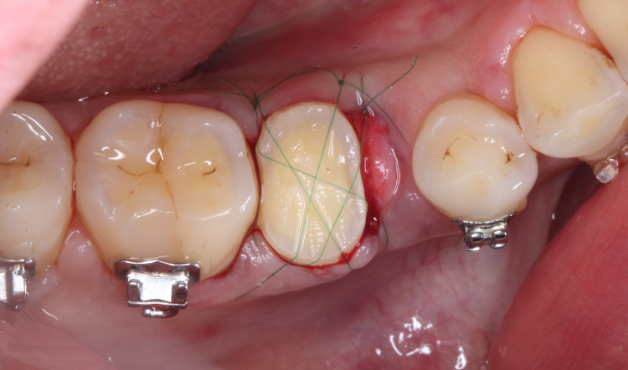

Under Treatment

主訴

歯を残せないと言われた。インプラントは先延ばしにしたい

治療内容

自家歯牙移植 / イニシャルトリートメント(大臼歯)レジンコア

治療期間

2ヶ月

治療費用

308,000

治療の

リスク

術後しばらくしてから骨性癒着、外部吸収を起こす可能性があります。